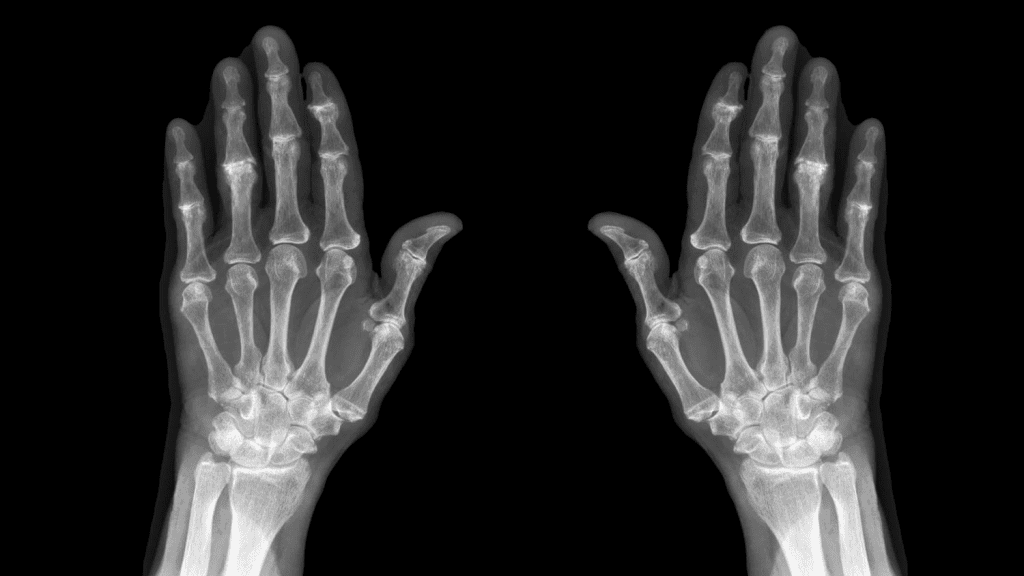

Hand and Finger Joint Imaging

X-rays are often used for hand and finger osteoarthritis. They show joint space narrowing and erosions. Ultrasound can also be used to evaluate joint inflammation and soft tissue changes.